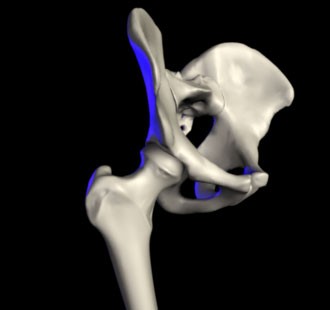

The hip is one of the most flexible joints of the body. It is a ball and socket joint formed between the proximal end of the femur bone and the acetabulum (or the socket) of the pelvic bone. This allows us to move our legs in a wide range of motion for a number of activities.

A surgical treatment involving the resurfacing of the joint. In the hip, the ball and socket are resurfaced, creating a smooth metal surface.2 This is an alternative to total hip replacement, which preserves more of the bone. In the knee, the patella and trochlea can be resurfaced to treat patellofemoral osteoarthritis.

For those affected by arthritis in the hip, a “hemiarthroplasty” replaces the ball and stem of the femur without replacing the socket on the pelvis. This is usually suitable for older people with a femoral neck fracture, rather than osteoarthritis.6